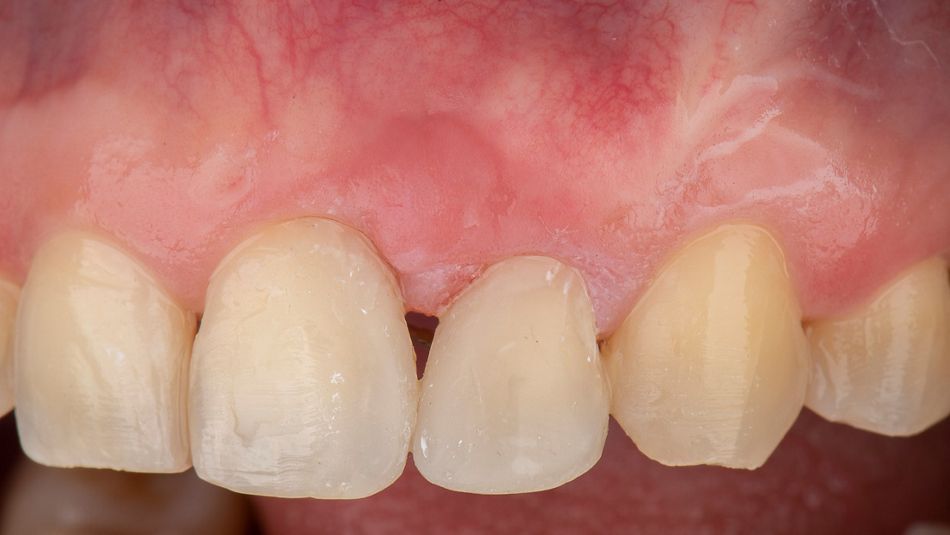

Control at 21 days post surgery (Fig. 12).

Fig. 12